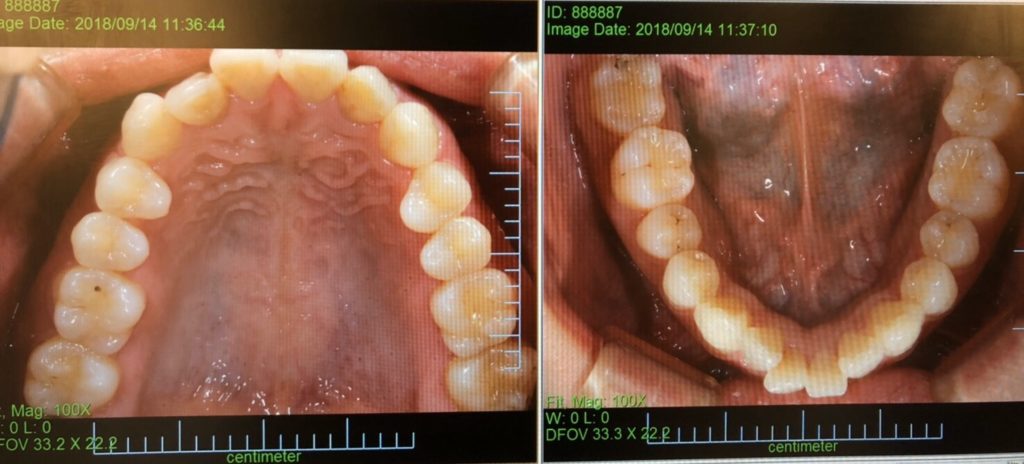

マウスピース(インビザライン)矯正スタートしました

こんばんは!パール歯科クリニック大江院歯科衛生士の倉岡です。矯正ブログへの投稿は初めてです!先週ついにインビザライン矯正をス… 続きを読む